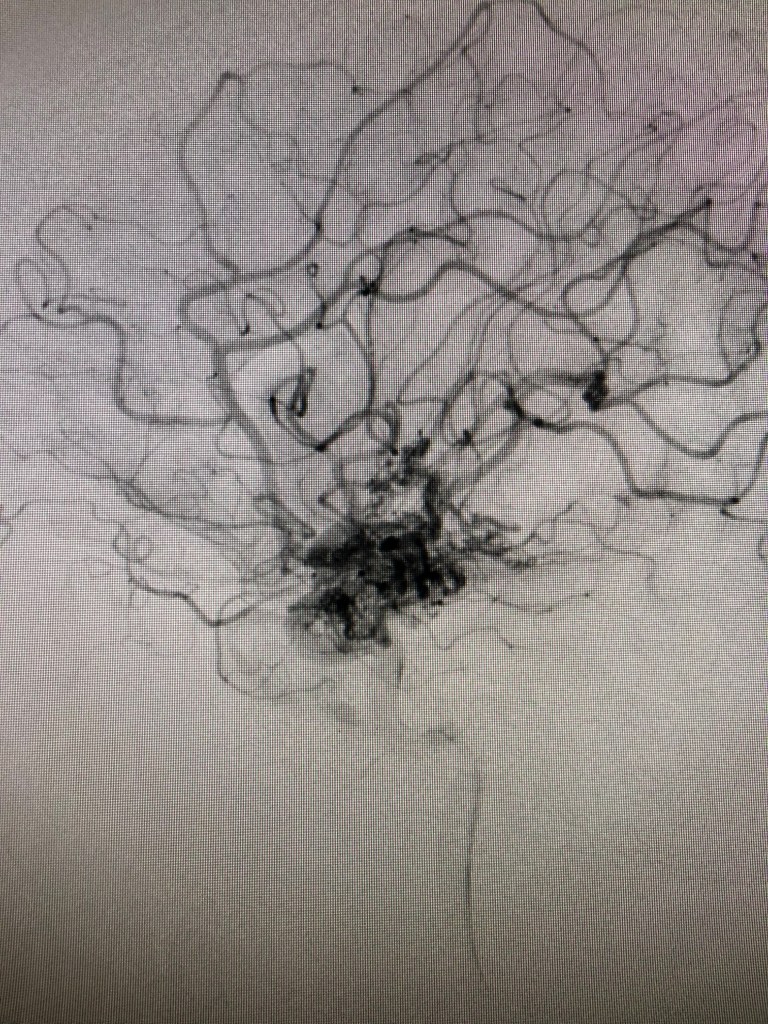

AVMs are commonly described as looking like a bird’s nest or a bowl of spaghetti noodles. In an AVM, the high-pressure arteries connect straight to low-pressure veins instead of the blood vessels connecting through a capillary as they should.